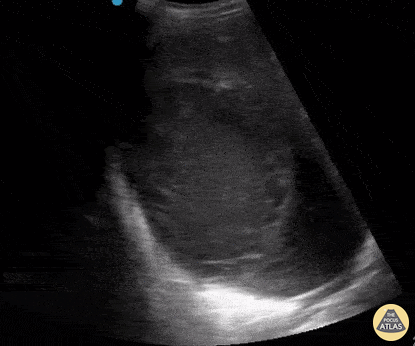

Biliary - Hepatic Abscess

A 50-year-old male presented with right upper quadrant pain, vomiting, and fever. A point-of-care ultrasound demonstrated a large, approximately 20cm heterogenous, well-demarcated mass in the liver. CT scan confirmed the presence of an abscess. IR-guided drainage yielded "anchovy paste" purulent aspirate, which later grew out Entamoeba histolytica. Amebic liver abscesses are the most common form of extra-intestinal amebiasis, but abscesses can also form in the lung and brain. He was treated with metronidazole without complications. Mark Zhang